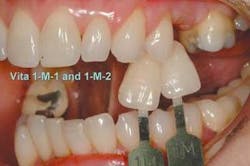

The impression, opposing models, two matching bite registrations, and shade tab photos were sent to Matt Roberts at CMR Dental Lab in Idaho Falls, Idaho, with instructions to make a Lava All-Ceramic System bridge with a ridge-lap pontic.

The ceramic build-up was started with the application of the porcelain margin material and some highly chromatic modifiers to camouflage the substructure. These layers were fired under vacuum in a porcelain furnace to full maturity. Subsequent layers of dentin and enamel powders were built and fired to replicate the optical qualities of the patient's natural dentition. Anatomical features were built in with a porcelain brush, rather than ground in with a high-speed handpiece, to create more natural contours. Final surface texture was achieved by grinding with a 850-016 diamond bur (Brasseler), then the bridge was fired to a low glaze. A diamond-impregnated rubber polishing wheel (Brasseler) was used to smooth areas to be highlighted, and diamond polish (Brasseler) accomplished the final surface luster. The bridge was fit to a fresh solid model to verify the interproximal contacts, tissue adaptation, and occlusion, then returned to Dr. Jones for delivery.